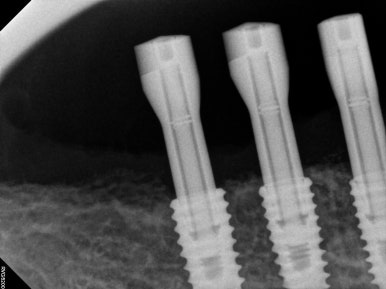

임플란트를 잇몸 안에 모두 묻어놓았기 때문에 (submerged) 추후에 임프란트 보철물을 연결할 수 있도록 치유지대주 (healing abutment)를 연결해주어야 합니다.

이 간단한 시술을 임플란트 2차 수술이라고 부릅니다.

임플란트 2차 수술을 얘기하면, 대부분의 환자분들이 또 수술을 해야하냐고 싫어하시지만... 임플란트 2차 수술은 학술적으로 보았을 때, 단순히 뚜껑을 하나 바꿔껴내는 행위는 아닙니다.

추후 제작될 임플란트 보철물 주변의 잇몸의 성상을 조성할 수 있고, 경우에 따라 잇몸이식술도 시행하여 보다 관리가 용이한 환경을 만들어내는 소수술이라고 보시는게 맞습니다.

아래턱 어금니 임플란트에 임플란트 2차 수술을 시행하고나서 약 10일 뒤 실밥을 제거합니다.

각 임플란트에 연결된 치유지대주를 제거하고, 스캔 바디를 연결한 뒤 구강스캐너를 사용하여 인상채득 (뽄뜨기)을 시행합니다.